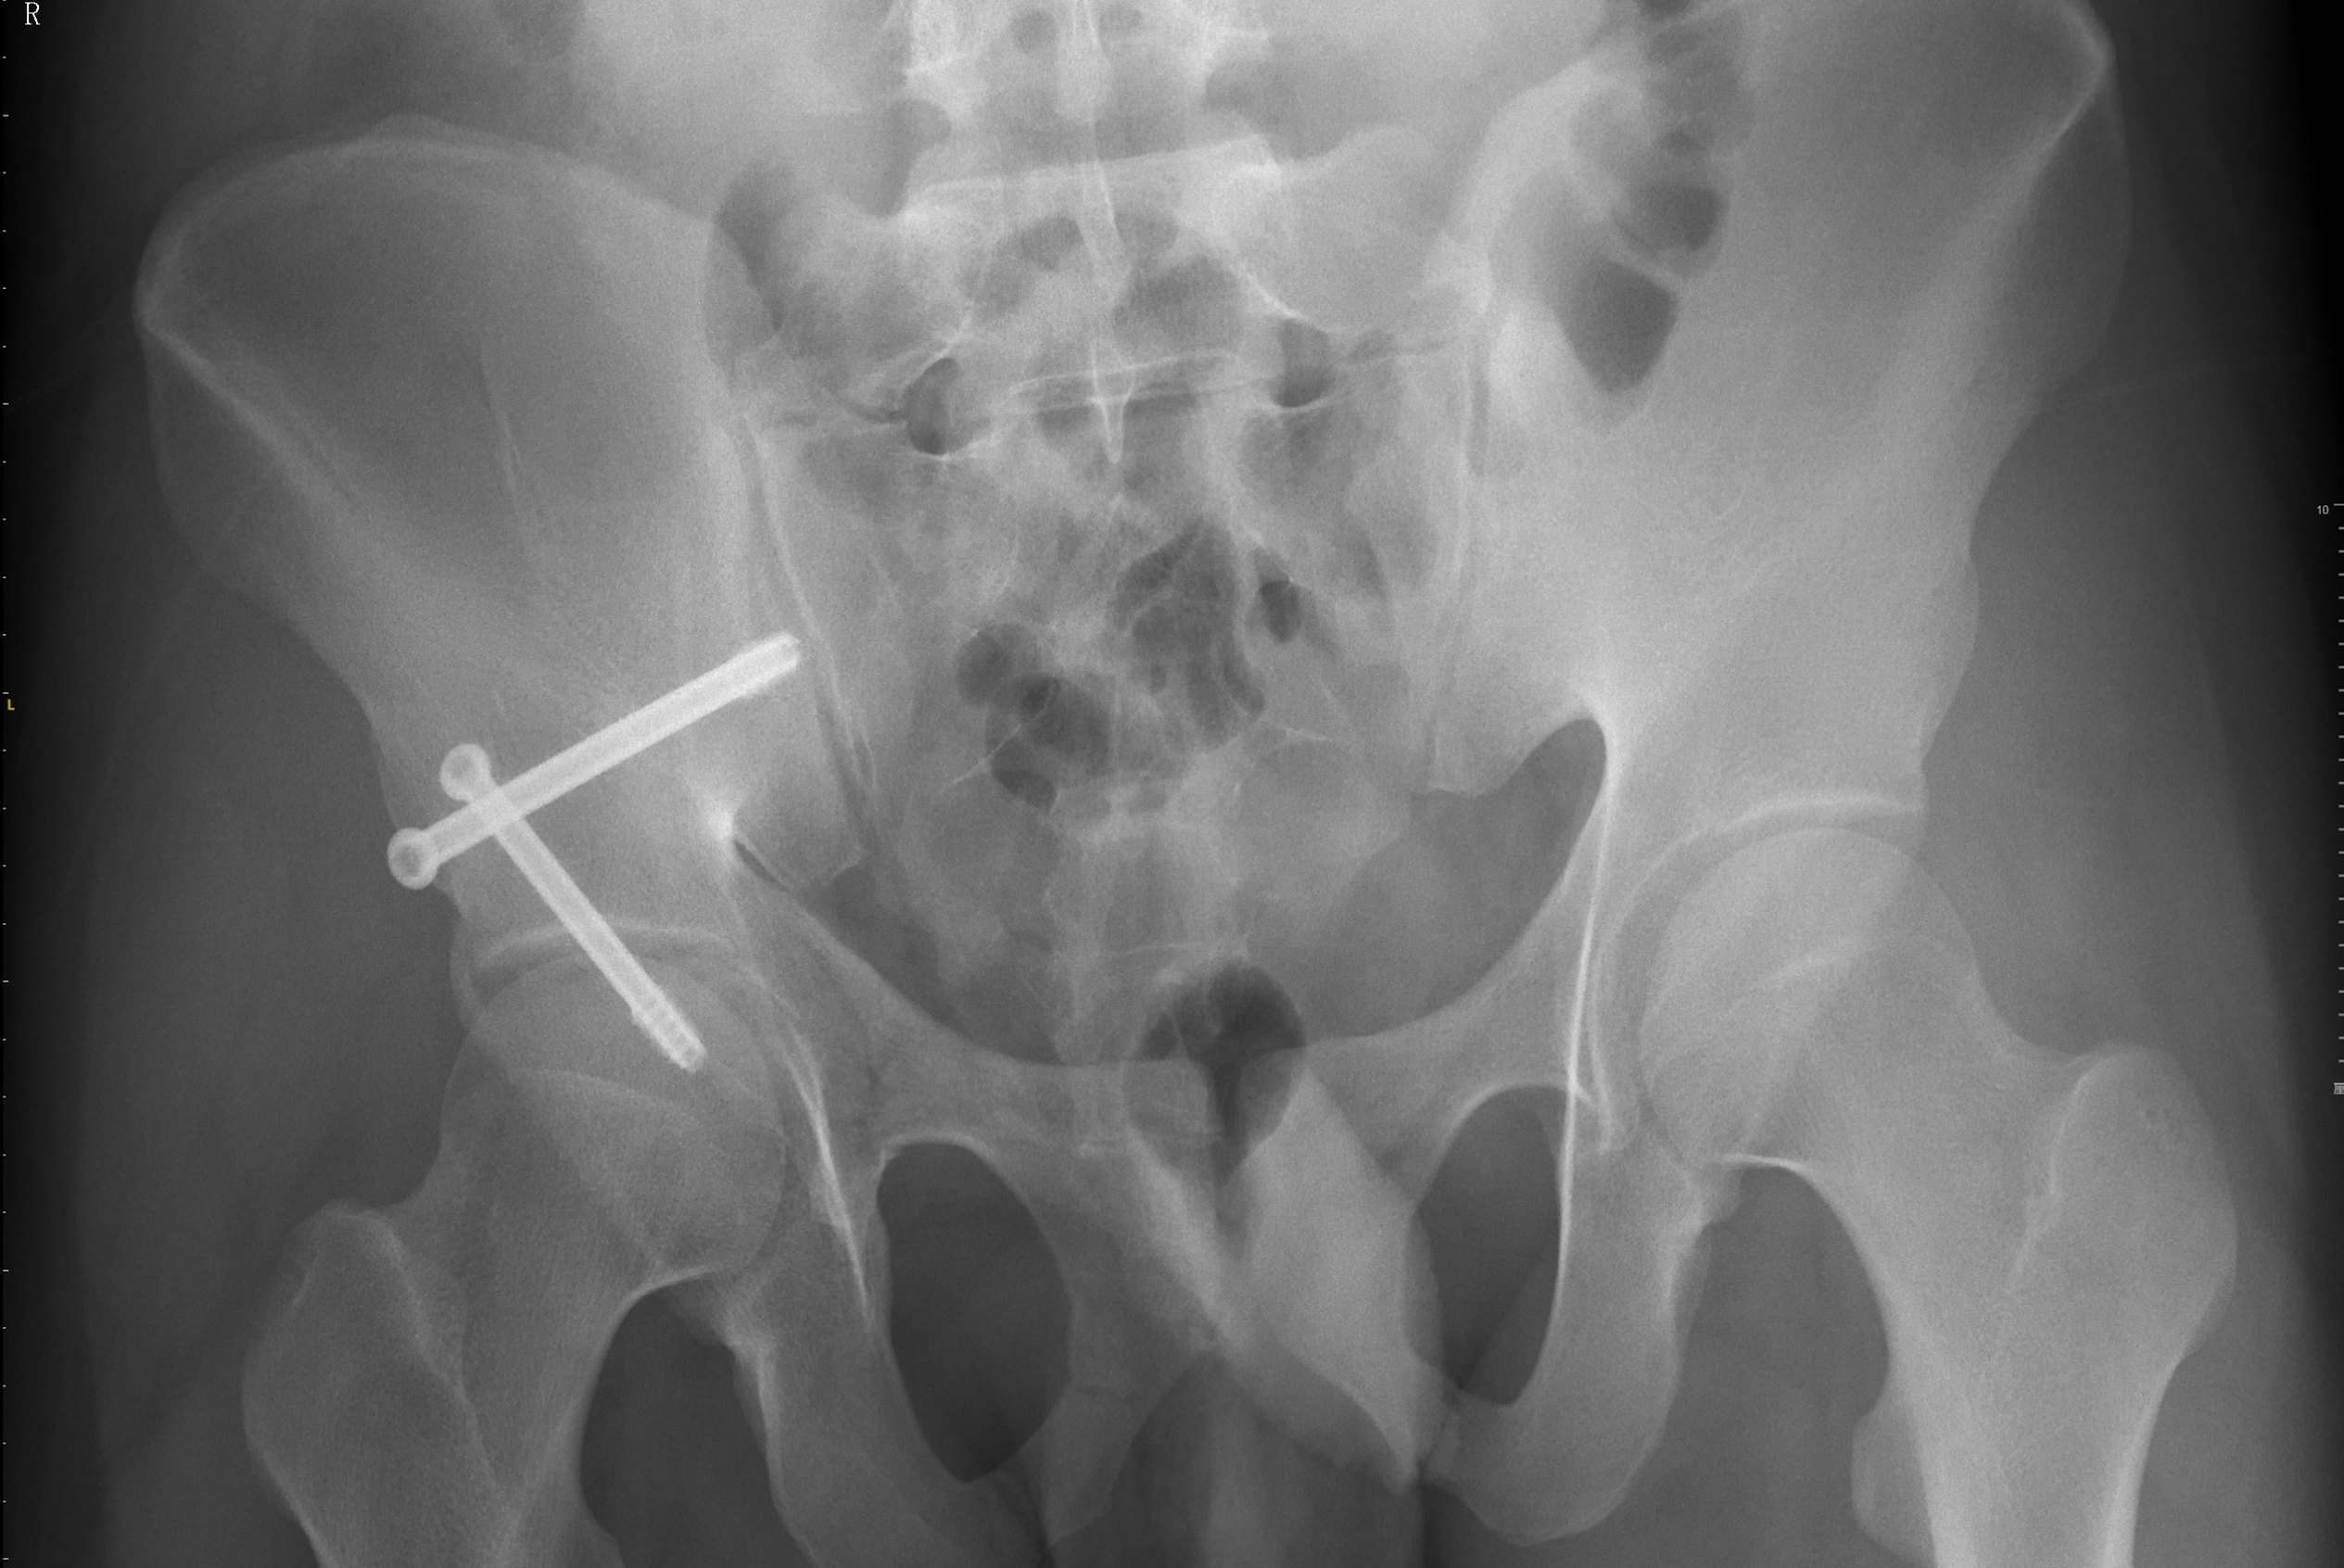

患者多处骨折影像资料

在潘勇卫主任医师的指导下,创伤骨科团队在术前对患者的髋臼骨折影像进行了讨论分析,并根据骨折情况进行了特异性手术规划,为患者设计螺钉通路。在手术执行过程中,赵喆副主任医师通过该设备实现在手术中全程“看到”术前重建的骨盆影像、骨折位置和规划螺钉置入的位置与姿态,并且通过提示信息指导术中C形臂摆位,在透视下精确地置入了两枚术前规划好的螺钉。患者术后复查的X线与CT影像均显示骨折复位和固定良好,且手术切口仅有不到3cm。

术后复查的X线片显示骨折复位和固定良好